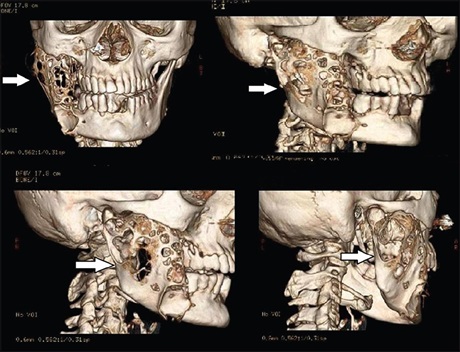

Computed Tomographic Assessment in Deep space Infections of Odontogenic Origin

Dr. Sankalp Verma, Ravi Prakash Sasankoti Mohan, Anchal Singh, Udita Singh, Neha Agarwal (Author)

64-67